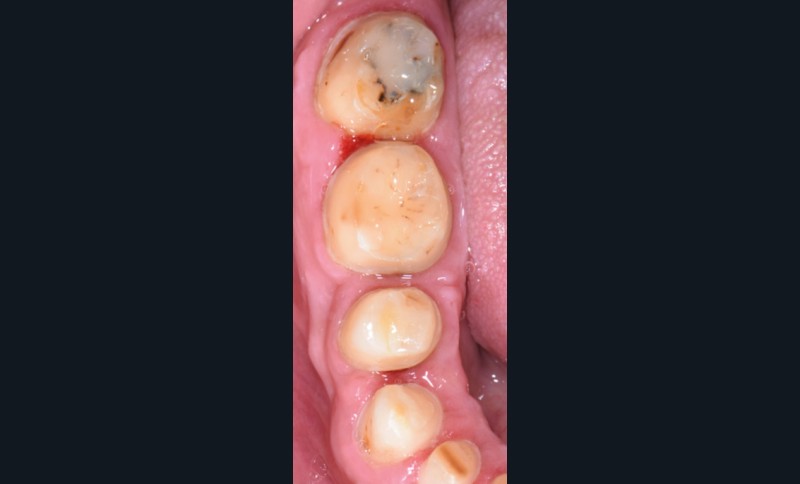

Au vu du contexte para-fonctionnel et de l’étendue de la perte tissulaire, des coiffes périphériques minimalement invasives ont été choisies afin de restaurer l’esthétique et la fonction. Actuellement, aucun consensus n’est fait sur le choix du matériau d’infrastructure à privilégier. Les matériaux hybrides usinables présentent des propriétés mécaniques, physiques et biologiques intéressantes en contexte d’usure sévère (e.g., module d’élasticité, résistance à la propagation de fêlures, facilité de réintervention). Une réhabilitation globale avec remontée de dimension verticale d’occlusion (DVO) par l’intermédiaire de coiffes composites renforcés en nano-céramiques est décrite.